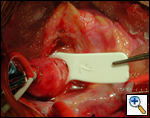

The operative approach is through a median sternotomy with the use of cardiopulmonary bypass and bicaval venous cannulation. The first dose of cold blood cardioplegia is antegrade; the remaining doses are retrograde.

High ascending aortic cannulation adjacent to the innominate artery for maximum exposure of the ascending aorta and to allow length for positioning of the patch in the ascending aorta.

One dose of antegrade cardioplegia followed by retrograde cardioplegia.

Pulmonary homograft or pericardial patches (tanned in glutaraldehyde) for the “shields”. These patches should not be too large – this will lead to aortic insufficiency.

First coronary sinus incision in noncoronary sinus to facilitate exposure of the incisions into the coronary orifice sinuses.

In most cases, the right coronary artery sinus should be opened to the left of the coronary orifice and the left coronary artery sinus to the right of the coronary orifice. Occasionally one may not have enough room between a coronary orifice and the aortic valve; in this case the incision site should be tailored to the situation.

Ensure similar orifice sizes between the proximal and distal ascending aorta after patch augmentation by the use of a sizing dilator.

Transesophageal echocardiography to assess completeness of repair, coronary blood flow postoperatively, wall motion abnormalities, and adequacy of aortic valve.